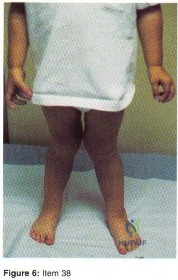

- Genu varum

- application of braces

- medial physeal stapling until the varus corrects

- observation

- application of corrective casts